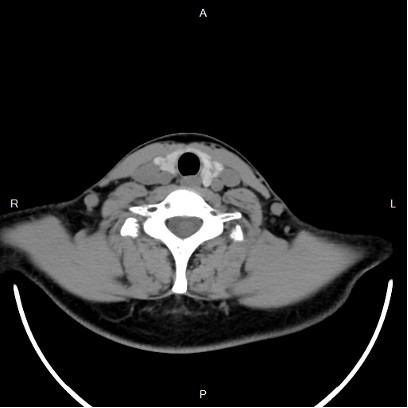

颈部CT提示:两侧甲状腺见多发的直径约2-3mm低密度灶,与周围甲状腺正常组织界限尚清晰。